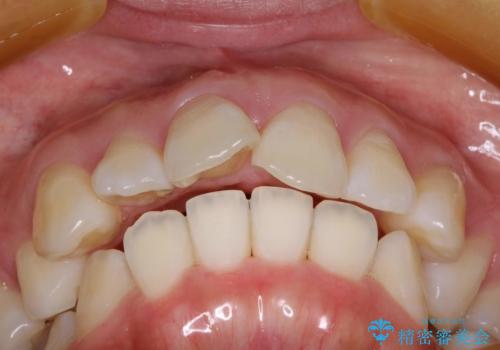

抜歯をして前歯を下げ、ガタつきを取り除く ワイヤー矯正

- 上顎両側第1小臼歯、下顎左側第2小臼歯の3本を抜歯、ラビアルのワイヤー矯正を計画した。

抜歯矯正は抜歯にできたスペースをつかい、前歯を積極的に下げたり、大きなガタつきを取り除くことができますが、その分時間がかかります。